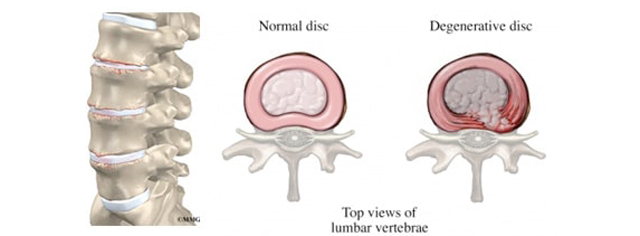

Dhembja te DDD

Dhembja e diskut të degjeneruar është ajo që pacientin e detyron të kërkojë ndihmë mjekësore. Dhembja zakonisht është e karakterit mekanik dhe atë si pasojë e shtypjes së rrënjëve nervore ose palcës kurrizore. Dhembja në fillim është e intensitetit të ulët dhe më e shprehur gjatë uljes apo qëndrimit të detyruar në një pozitë dhe përkeqësohet gjatë aktivitetit të shtuar, por që zvogëlohet gjatë pushimit.

Dhembja mund të jetë e lokalizuar në qafë, që përcillet edhe kah krahët dhe koka, por mund të jetë edhe në mes-bel, e cila përcillet edhe kah kërdhokullat, vithet dhe kah kofshët.

Këto dhimbje zakonisht janë të karakterit përsëritës me përmirësime dhe përkeqësime. Dhimbja akute e bën të vështirë lëvizjen normale të shpinës. Në disa raste, sëmundja degjeneruese e diskut gjithashtu shkakton dobësi, mpirje dhe ndjenje të të nxehtit, dhimbje në krahë ose këmbë (dhimbje radikale)

Në rastet kur si pasojë e DDD shkaktohet komprimim i rrënjëve nervore si pasojë e stenozes, preferohet vetëm dekomprimimi i rrënjës së nervit të shtypur në raste të posaçme edhe stabilizimi i unazave me vida, pastaj sot aplikohen edhe disqet artificiale (disc replacement cage) si në unazat e qafës, kraharorit, ashtu edhe në ato të mesit.